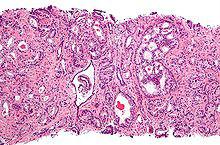

①Gleason 1級(很少見):一致性規則的大腺體,背靠背密集,形成小結節。

②Gleason 2級:較不規則的大腺體,背靠背密集,形成小結節,結節內腺體不融合。

③Gleason 3級:浸潤性生長的小腺體或腺泡,或小型篩狀結構腺體。

④Gleason 4級:融合腺體,大型篩狀腺體,或呈腎透明細胞癌樣。

⑤Gleason 5級:實性癌巢(無腺樣結構),單個癌細胞浸潤,或呈粉刺樣癌(癌細胞壞死)。

圖1 類型1 邊界清楚的結節,結節內腺體結構和大小一致,排列緊密,間質很少,每一腺體是獨立的。

圖2 類型2 邊界比較清楚的結節,與結構類型1相比,結節內腺體結構和大小較不一致,腺體之間距離增加。

圖3 類型3 形態和大小明顯不規則的腺體在較寬的間質和良性腺體間浸潤,腺體保持獨立,中等至較大的腺體為主的區域稱3a,小腺體為主者稱3b。

圖4 類型3 界限清楚的、外形光滑圓鈍的腔內形成乳頭狀和中等大小篩狀結構,是3c的特點,注意緊鄰的小團小腺體。

圖5 類型4a 腺體融合,形成不規則的、具有篩狀結構的腫瘤細胞片團。

圖6 類型4a 另1病例,顯示融合的腺腔和篩狀結構可有較大變異。

圖7 類型4b 由胞質透亮、核小而深染的腫瘤細胞形成的片狀結構,形似腎透明細胞癌,又名hypernephroid結構類型。

圖8 類型5a 融合的腫瘤細胞團中央開始出現粉刺狀壞死。

圖9 類型5b 索狀或單個腫瘤細胞浸潤,缺乏腺腔結構。